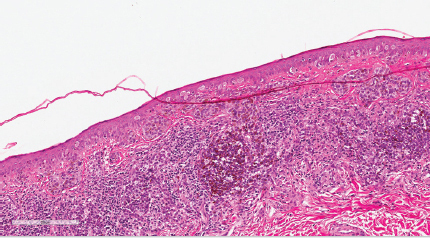

Clinical information can be crucially important in the diagnosis of melanoma. Older patient age, increased signs of solar damage, and large lesional diameter (> 6 mm) will immediately alter the perspective through which a biopsy is reviewed. Numerous criteria are considered, both in number and severity, in the assessment for malignancy. In general, melanomas tend to show many forms of asymmetry. These include asymmetry of low power silhouette, lateral border cell distribution, cytologic features, pigmentation, inflammatory host response, and nesting architecture. Consumption of the epidermis (

Fig. 11.8e) and pagetoid spread of melanocytes (

Fig. 11.10) are emblematic clues to melanoma.30